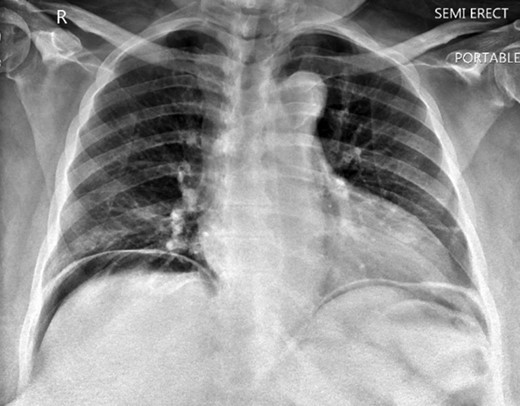

A 63-year-old African American female presented with complaints of abdominal pain located more in the right lower quadrant and multiple episodes of vomiting for the past 4 days. She had a history significant for ventral hernias and past surgical history of two myomectomies. Physical exam demonstrated right upper and right lower abdominal tenderness and peritoneal signs. Patient had fever and tachycardia. Chest x ray showed free air under the diaphragm (Fig. 1). Computer tomography revealed pneumoperitoneum and alarge gas containing collection in the pelvis measuring 13.6 Ă— 8.8 cm2. This was in close proximity to the sigmoid colon which appeared thickened, and extending to the right adnexal region (Fig. 2A and B). Laboratory results showed white blood cell count 28.7 Ă— 103/ ÎĽL, 93% neutrophils. The patient was taken to the operating room for exploratory laparotomy with the presumptive diagnosis of perforated sigmoid diverticulitis.

(A) Computer tomography showing pelvic collection. (B) Computer tomography showing pneumoperitoneum.